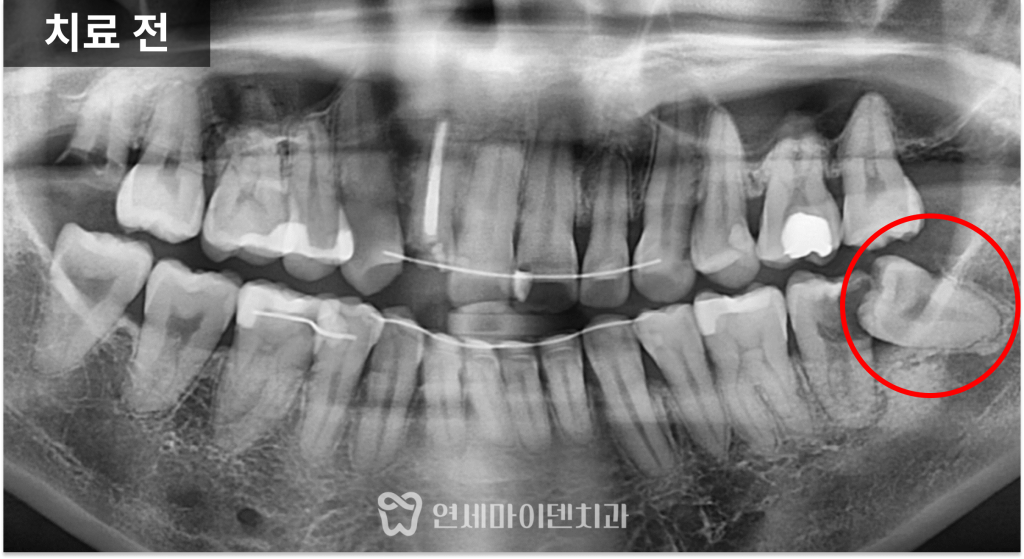

방사선 사진에서 확인해 보면

사랑니가 정상적으로 올라오지 못하고

앞쪽 어금니 방향으로 누워 있는 상태였습니다.

이렇게 기울어진 사랑니는

칫솔이 닿지 않는 사각지대를 만들고,

음식물이 지속적으로 끼면서

충치가 발생하기 쉬운 환경이 됩니다.

특히 문제는 사랑니 자체보다

앞쪽의 정상 어금니에 손상을 준다는 점입니다.

이번 케이스에서도

사랑니와 맞닿아 있는 앞 어금니가

이미 깊게 썩어 있는 상태였습니다.